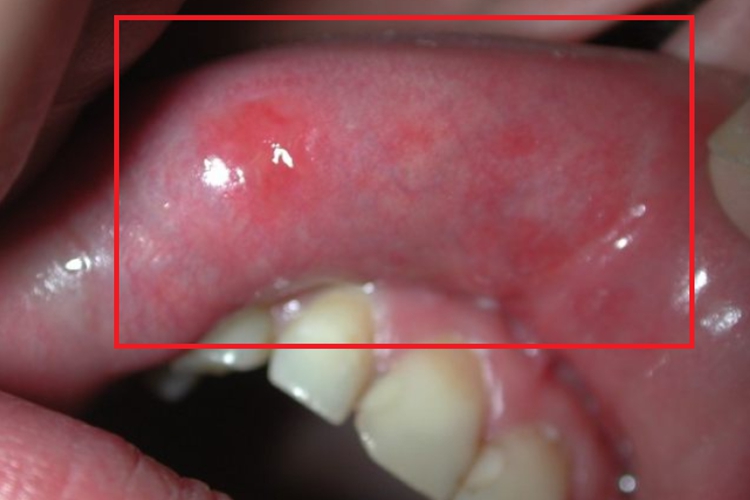

颌面部获得性梅毒可发生在唇内侧,表现为形状不规则的红斑,大小、数量不等,分布无具体规则,边界模糊,红斑表面光滑且红肿,质地稍硬。